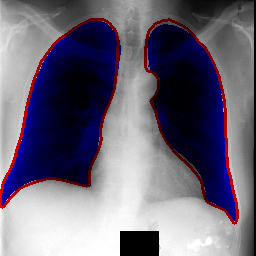

Repository features UNet inspired architecture used for segmenting lungs on chest X-Ray images.

Scores achieved on Montgomery and JSRT(With these masks. See preprocess_JSRT.py.) (Measured using 5-fold cross-validation):

| IoU | 0.971 | 0.956 |

| Dice | 0.985 | 0.972 |